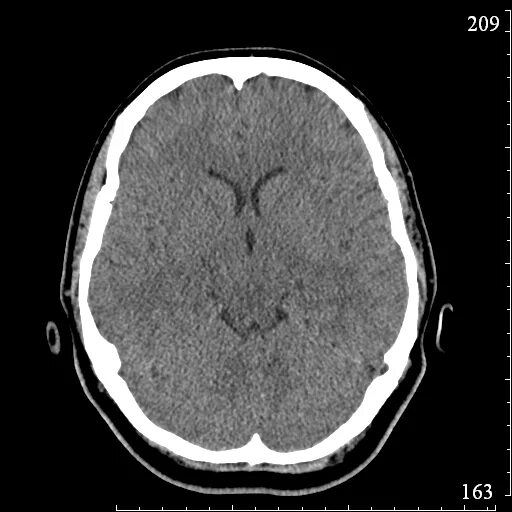

Глиозные изменения головного мозга на мрт